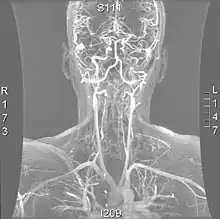

Os métodos mais modernos envolvem angiografia por tomografia computorizada, denominada angiotomografia (ATC ou angio-TC) — e ressonância magnética (RM). Estes métodos requerem uma menor quantidade de contraste e não são invasivos. A angiografia por TAC e a angiografia por RM são mais ou menos equivalentes quando usadas para diagnosticar ou excluir uma dissecção da artéria vertebral.[13] A ATC tem a vantagem de mostrar certas anormalidades mais cedo, tende a estar disponível fora do horário de expediente e pode ser realizada rapidamente.[1] Quando a angiografia por RM é usada, os melhores resultados são obtidos no cenário T1[2] usando um protocolo conhecido como "supressão de gordura".[3] A ecografia Doppler é menos útil, pois fornece poucas informações sobre a parte da artéria próxima à base do crânio e no forame vertebral, e qualquer anormalidade detectada na ecografia ainda exigiria confirmação através de um TC ou RM.[1][2][3]